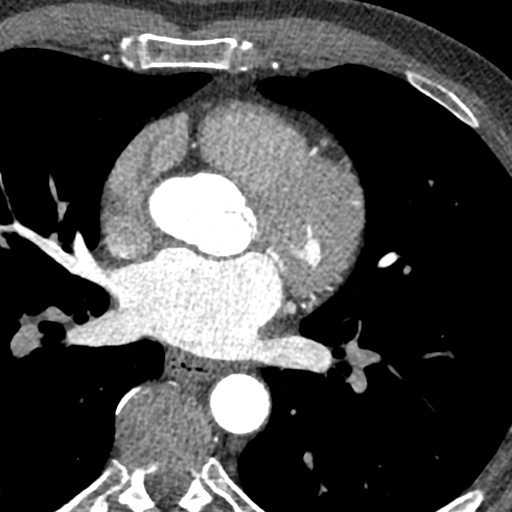

- May 19 2021. The Cardiologists

To add to the saga of cancer

Something else appeared in the scans

Something that needed an answer

Something that could derail our plans

It was first seen in 2016

Did not seem to be a big threat

Now it was time for a screen

For me it just added more sweat

A two cardiologist inspection

With CT Scan imagism

Proximal celiac artery dissection

With a 1.3 cm aneurysm

But finally here was a break

I was under no imminent danger

My heart was in really good shape

This was really no big game changer